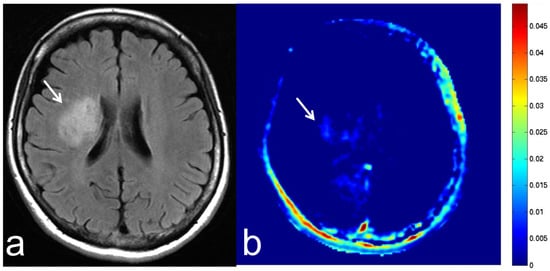

5.5. Brain Metastasis

6. APT-CEST Imaging of Meningioma